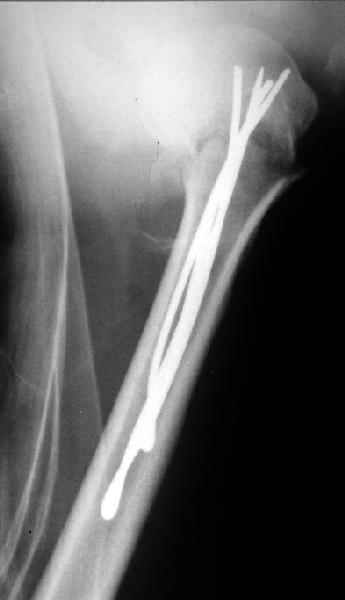

Сегодня взял больного повторно в операционную, не скажу, что повторная репозиция через неделю после первой попытки, была простая.

После удаления спиц попытался манипулировать отломками, но безуспешно, поэтому пришлось пользоваться периостальным элеватором, чтобы устранить смещение отломков и перепровести спицы. Проверил и перепроверил стабильность фиксации под ЭОПом, завтра Рг- будет готов, вот и поглядим....

Да. У нас довольно скромный опыт такого остеосинтеза (по 2 случая - плечо и наружная лодыжка), дошли до использования самого простецкого троакара, через который мы сверлим кость и вводим 6 мм стержни, когда накладываем аппарат. Соответственно, в качестве забойника отлично работает любой стержень от аппарата Илизарова. Еще из наших туземных особенностей - страшная любовь к спицевым дистракторам, поэтому делали в нем. Результат у этой дамы неизвестен, т.к. она из области и уехала рожать сразу после остеосинтеза, сейчас прошло больше 5 месяцев...

Что-то, наверно, сделали мы не совсем оптимально, поскольку у Анатолия Федровича и его соратников как-то красивее "раскрываются" спицы в головке плеча - надеюсь, он прокомментирует и подскажет, что надо подправить.